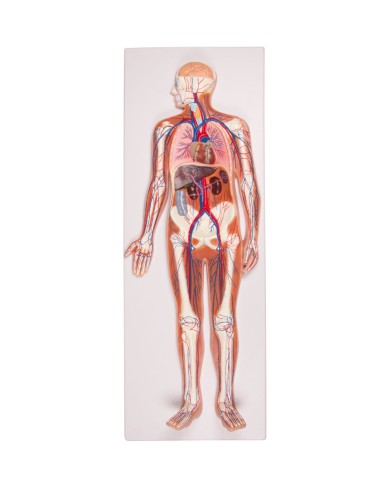

Kit composto da 3 modelli

Su tavola, con supporto e istruzioni per l'insegnamento. Con colorante rosso e siringa di riempimento.